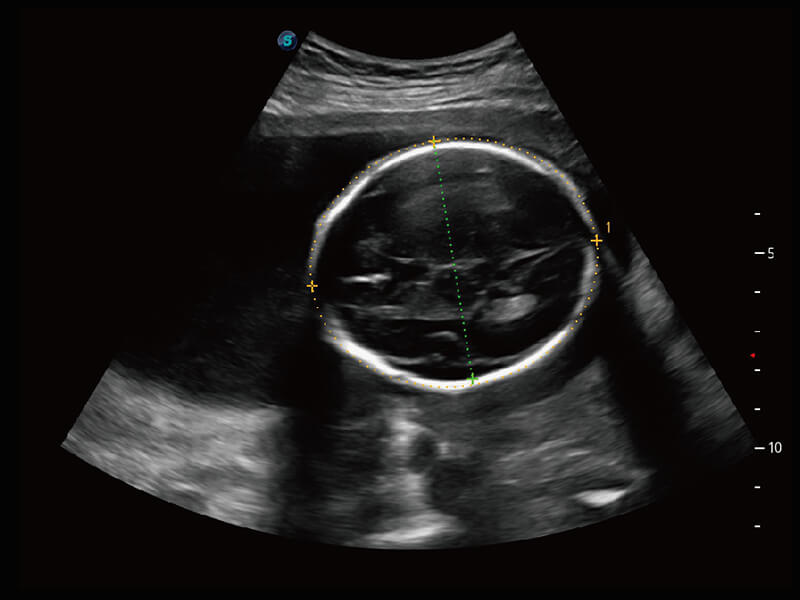

S60探头工艺,从前端信号处理每一个环节采集无损声学数据,真实还原组织原貌,再现解剖细节。

S-Fetus 产科扫查助手

准确率

按键操作